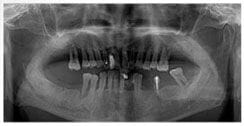

X 光片

術前X光片

術後X光片